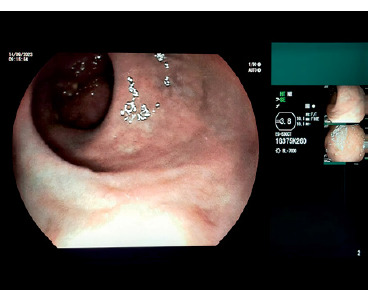

New challenges in the management of inflammatory bowel disease: a case study.